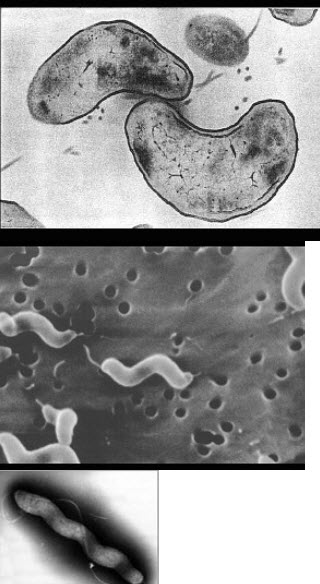

13、单项选择题

关于图中所示的弯曲菌,叙述正确的是()

A.抗原结构简单

B.属有动力、无芽孢的革兰阴性逗点状菌

C.厌氧菌

D.在低温条件下生长

E.对外界抵抗力强